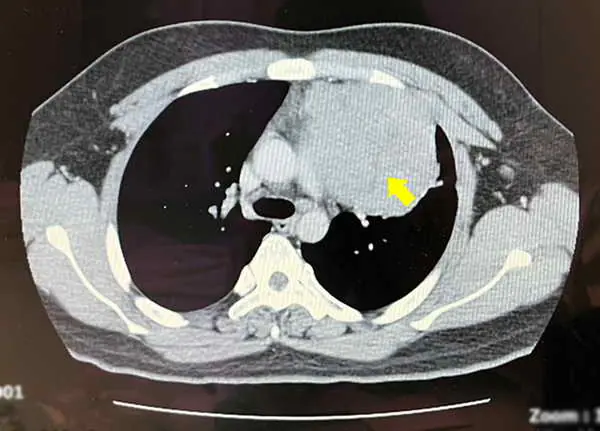

賴重佑部主任確認在前縱膈腔偏左,有一顆12公分且高度疑似為惡性的腫瘤。先安排患者入院檢查,包括做切片先確認腫瘤性質,接著進行胸部核磁共振造影以確定沒有侵犯心包膜,及腫瘤與心臟、肺臟的黏著程度。另外考量腫瘤疑似生殖細胞瘤,也做了腹部斷層掃描,確認肚子沒有其他腫瘤存在,在一連串深度檢查後確定是罕見的縱膈腔精細胞瘤。

圖二:患者在術前檢查X光(紅圈處是腫瘤)。